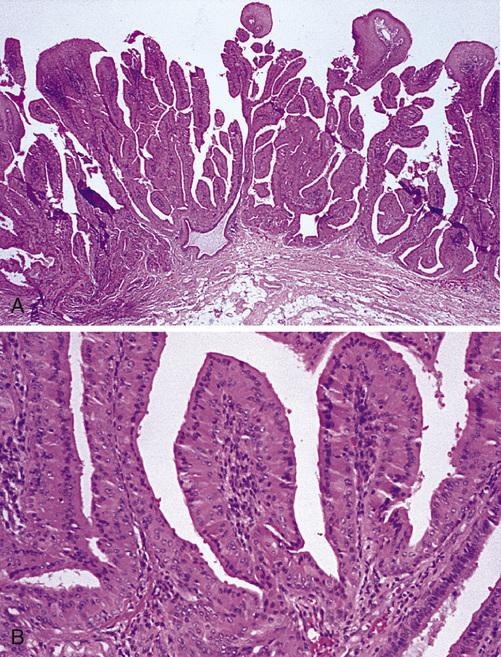

Low-power view showing a papillary cystic tumor with a lymphoid stroma. The epithelium is oncocytic, forming uniform rows of cells surrounding cystic spaces.

Warthin tumor

High-power view of epithelial lining showing double row of oncocytes with adjacent lymphoid stroma. The inner luminal layer consists of tall columnar cells with centrally placed, palisaded, and slightly hyperchromatic nuclei. Beneath this is a second layer of cuboidal or polygonal cells with more vesicular nuclei.

Warthin tumor